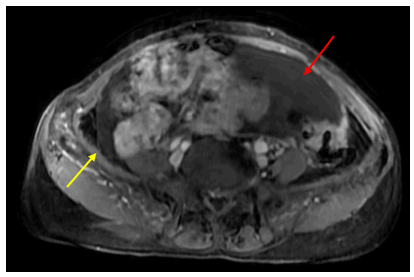

Chụp CT ổ bụng có tiêm thuốc cản quang:

Hình 1: Hình ảnh khối vùng tiểu khung kích thước 52x69mm (vòng tròn đỏ).

Hình 2: Dày lan tỏa phúc mạc, ngấm thuốc mạnh sau tiêm (mũi tên đỏ).

Hình 3: Dịch tự do ổ bụng, chỗ dày nhất 53 mm (mũi tên vàng).

Chụp CT lồng ngực:

Hình 4: Hình ảnh vài dải xẹp phổi thùy dưới phổi hai bên. Ít dịch màng phổi trái

10 mm (mũi tên đỏ).